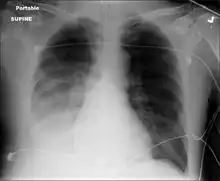

Pneumococcal antigen (cell wall C polysaccharide) may be detected in various body fluids. Older detection kits, based on latex agglutination, added little value above Gram staining and were occasionally false-positive. Better results are achieved with rapid immunochromatography, which has a sensitivity (identifies the cause) of 70–80% and >90% specificity (when positive identifies the actual cause) in pneumococcal infections. The test was initially validated on urine samples but has been applied successfully to other body fluids.[28] Chest X-rays can also be conducted to confirm inflammation though are not specific to the causative agent.[29][13]

Chest X-ray pneumonia